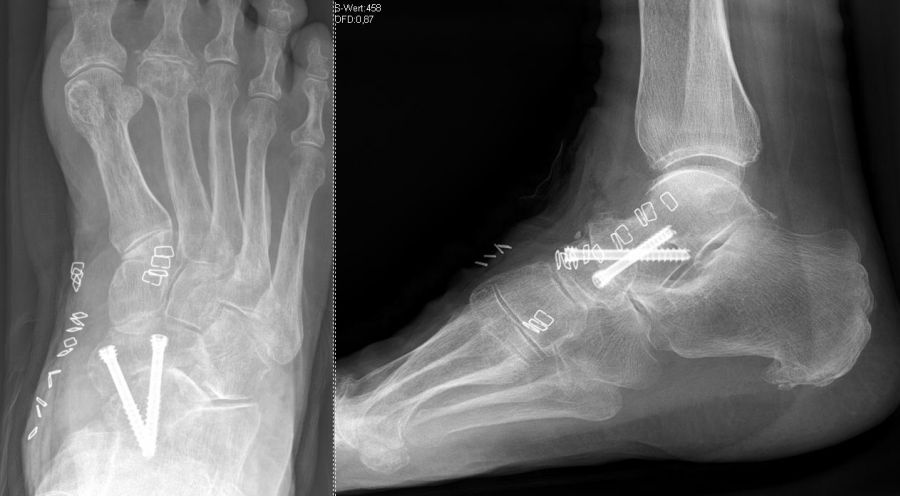

Es kommen verschiedene technische Möglichkeiten der operativen Versorgung in Frage.  Verwendung finden vor allem winkelstabile Plattensysteme, Schraubenosteosynthesen, Klammern, intraossäre Nagelsysteme, temporäre Kirschnerdraht-Transfixationen, Einbolzen von trikortikalem Span und Anlagerung von Spongiosa aus dem Beckenkamm oder dem Tibiakopf  (Abb. 2 und 3).

Die isolierte Arthrose der Bona Jäger Gelenkreihe (navikulocuneiforme Gelenk) ist selten und oft posttraumatisch. Meistens geht die navikulocuneiforme Arthrose mit einem schmerzhaften Pes planovalgus einher 2425. Letztlich werden die betroffenen Gelenkflächen angefrischt und mittels verschiedener Implantat-Möglichkeiten (s.o.) fusioniert. Bei gleichzeitiger Plattfußfehlstellung sollte diese ebenfalls adressiert werden 26 (Abb. 4). Ziel ist die Arthrodese in anatomischer Stellung der Gelenke.